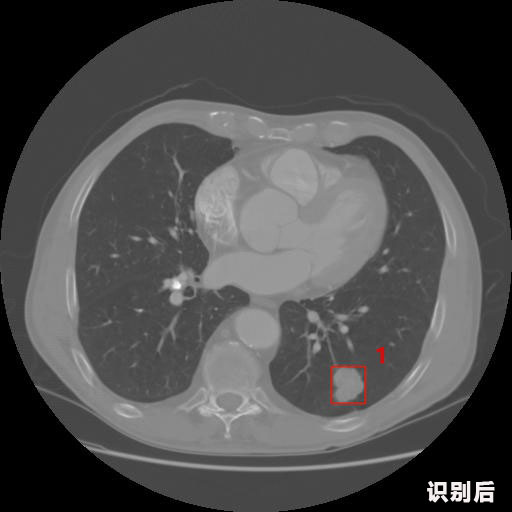

英特健康A(chǔ)I深度學(xué)習(xí)醫(yī)療圖像識別系統(tǒng)案例_胸部CT

1.發(fā)現(xiàn)肺結(jié)節(jié)的可能性為95.56%---位于框指數(shù)位置:[331.70554 366.13406 365.21707 403.96234]